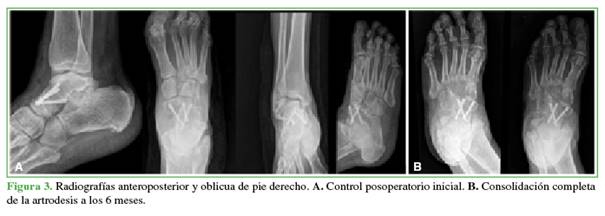

Las radiografías iniciales mostraron una luxación astrágalo-escafoidea de tipo giratorio hacia medial con impactación del escafoides tarsiano en la superficie articular anterior del astrágalo y una fractura del cuboides. Se solicitó una tomografía computarizada para buscar lesiones asociadas y la planificación quirúrgica (Figura 2). Ante este caso crónico y la lesión osteocondral, se optó por la reducción abierta de la luxación y la estabilización con artrodesis e injerto óseo.

Al concluir el seguimiento a los 18 meses, el paciente tenía un pie estable, plantígrado, no doloroso y el puntaje de la American Orthopaedic Foot and Ankle Society era de 87. En la Figura 3, se muestra la consolidación completa de la artrodesis.